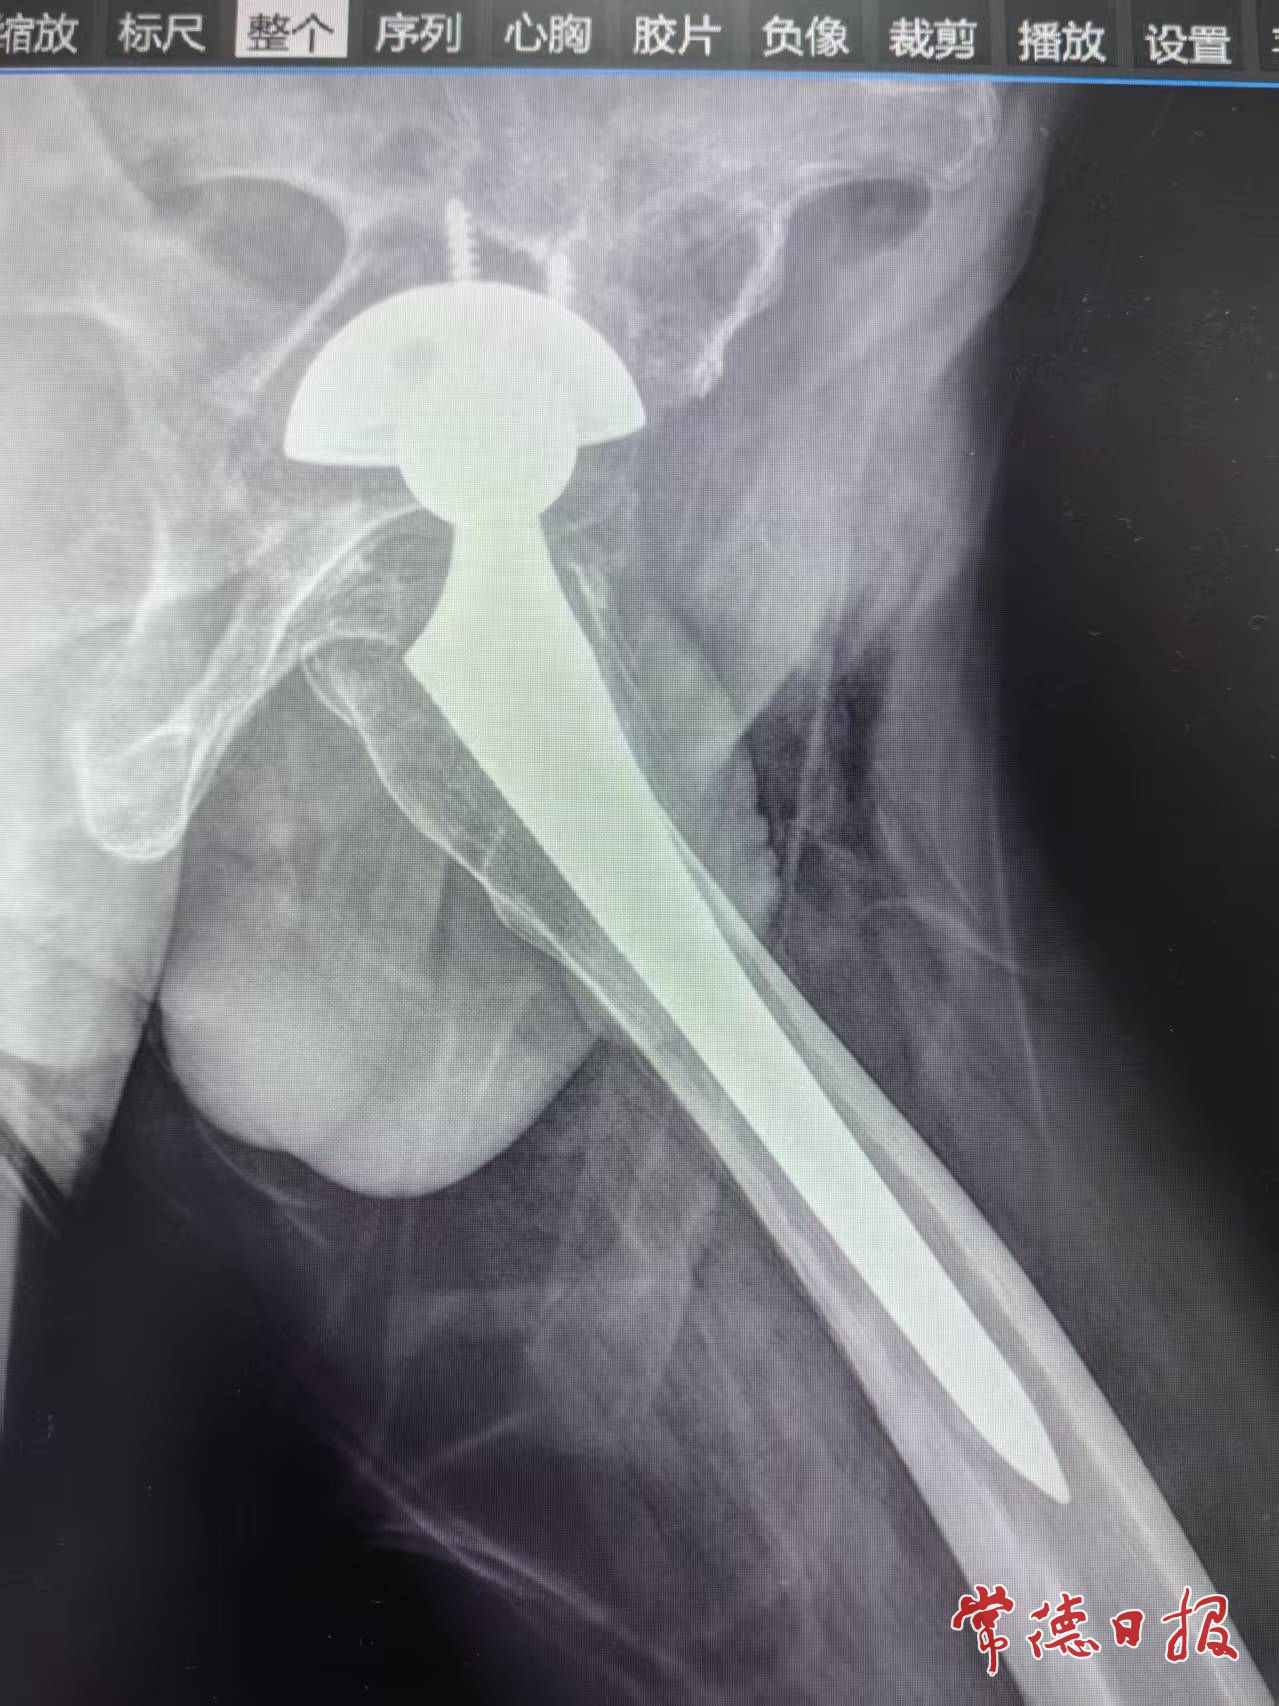

经检查,唐大爷被确诊为“全髋关节置换术后髋臼假体松动”。影像资料显示,其髋臼假体周围出现了大量骨缺损,这意味着初次置换的关节已无法继续使用,必须进行二次“重启置换”。

在麻醉科的紧密配合下,手术团队凭借精湛的技术,小心翼翼地将已松动的旧假体取出,精准清理关节腔后,采用合适的植骨材料对缺损部位进行修复,并成功为唐大爷植入了新型适配的髋臼假体。整个手术历时仅2小时,过程精准、出血量少。术后第二天,唐大爷便能开始在床上进行功能锻炼;术后第三天,他已能借助助行器下地行走。